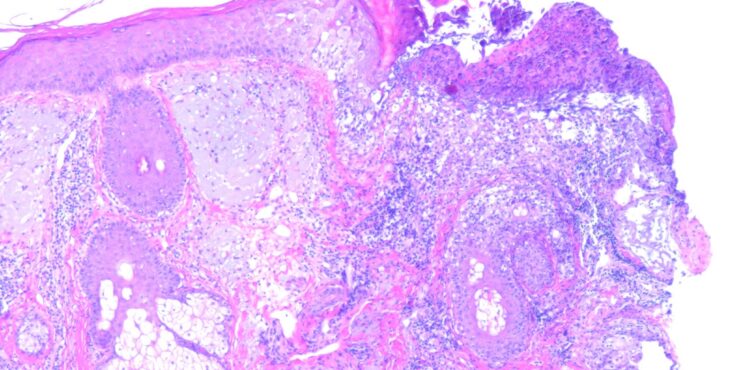

Herpes simplex = العقبول البسيط

Herpes simplex = العقبول البسيط OLYMPUS DIGITAL CAMERA OLYMPUS DIGITAL CAMERA OLYMPUS DIGITAL CAMERA OLYMPUS DIGITAL CAMERA OLYMPUS DIGITAL CAMERA OLYMPUS DIGITAL CAMERA OLYMPUS DIGITAL CAMERA OLYMPUS DIGITAL CAMERA OLYMPUS DIGITAL CAMERA